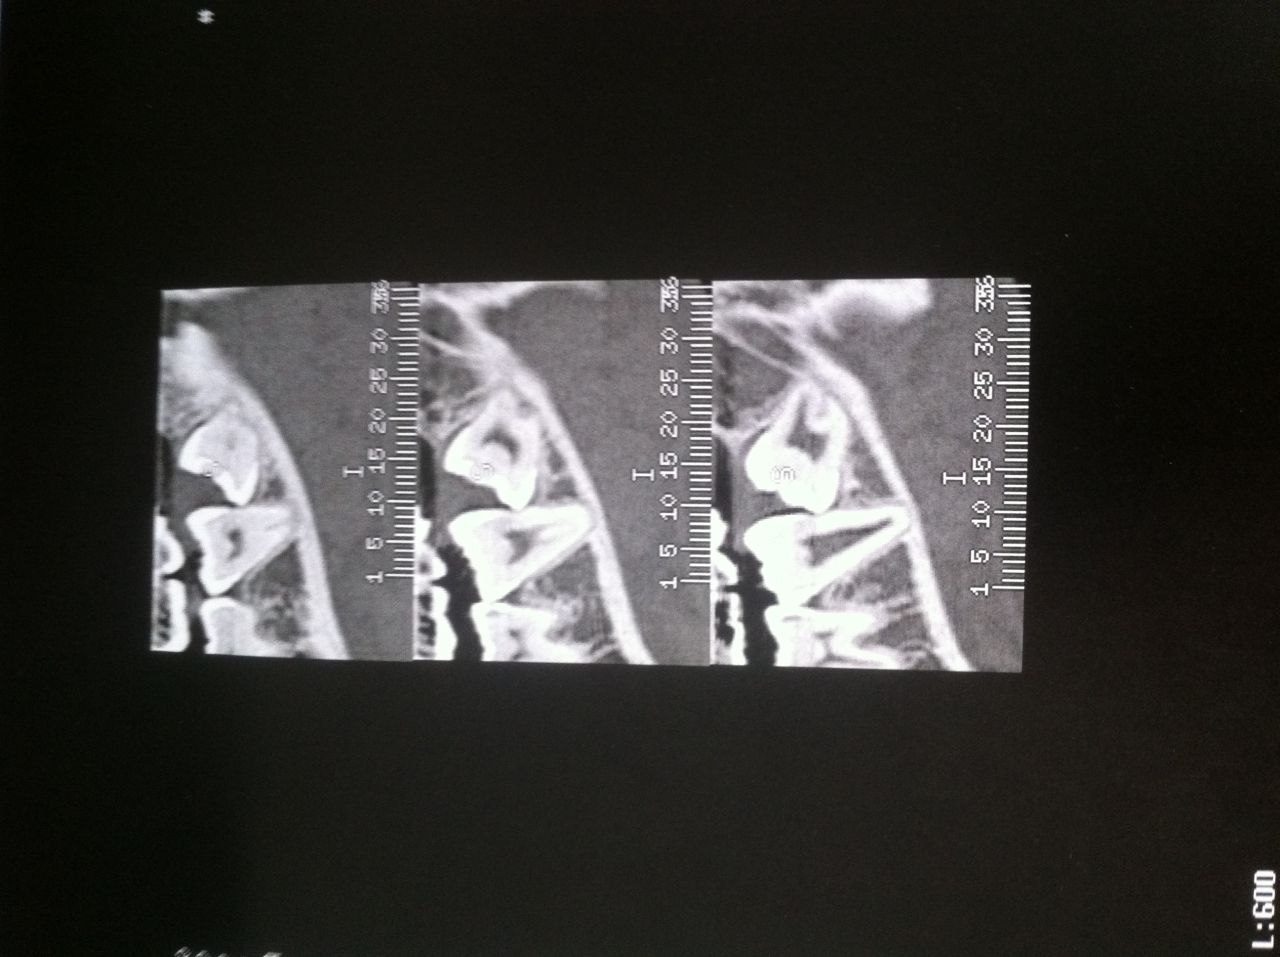

Déconnecté | Je suis allez chez le dentiste ce matin, il a pas regardé bien longtemps, il à coupé un fil parce que c'était irrité tout autour, il pense que je n'ai pas supporté le fil. sur le coup ça m'a soulagé mais j'ai de nouveau mal. J'ai eue des anti douleurs et un gel anésthésiant à appliquer directement. donc heureusement moins grave que ce que je pensais, moi qui suis parano. vanessa : Pour ma dent à l'horizontale qui passait près d'un nerf (ou le nerf qui passe près de la dent ) en plus de la radio j'ai du faire un scanner (je coute cher à la sécu) |

| Dire merci | ah bon ??? nan ??? purée j'espère que j'aurai pas un scan à faire ![]() voici le plus beau sourire colgate : ![]() La dent de sagesse à l'horizontale en bas à droite et celle du dessus cariée bien comme il faut Maintenant reste à appeler le chir ... je flippe ![]() mais pas le choix ! |